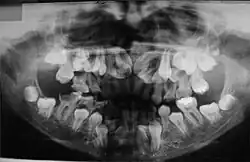

No estudo realizado por McNamara et al. (1999) sobre as características da síndrome, encontradas nas radiografias panorâmicas, citam-se a presença de múltiplos dentes não irrompidos; dentes com alterações de forma; ramos ascendentes da mandíbula delgados com os bordos posterior e anterior paralelos e, em alguns casos, estreitando-se em direção ao processo coronóide e côndilo; processo coronóide frequentemente ascendente e para posterior; arco zigomático estreito com severa inclinação descendente e algumas vezes descontínuo com a sutura zigomático-temporal; seios maxilares pequenos ou ausentes; bordo infraorbital mais baixo que o normal em relação aos dentes; inclinação descendente do assoalho da fossa nasal em relação à espinha nasal anterior, acentuando a forma em V; trabeculado ósseo da mandíbula com aspecto grosseiro; aumento da densidade da crista óssea alveolar, comprometendo a irrupção dentária; aumento da densidade do ramo ascendente entre o bordo anterior da mandíbula e o canal dentário inferior. A maior parte dos pacientes com disostose cleidocraniana desempenha suas funções normais, não apresentando comprometimento significativo. Existem relatos de que o tratamento cirúrgico com a exposição dos dentes inclusos, combinado com o tratamento ortodôntico, tem sido bem-sucedido em alguns casos (McDONALD, 2001). Porém, a extração dos dentes decíduos não promove a erupção dos dentes permanentes inclusos.[11]

Sabe-se que a retenção prolongada dos dentes decíduos, agenesias e dentes supranumerários provocam má oclusão. Portanto, procedimentos ortodônticos devem ser utilizados com a finalidade de adequar a cavidade bucal para futura reabilitação protética. Os exames radiográficos, além de auxiliar na detecção das anormalidades maxilofaciais, permitem o acompanhamento dos pacientes, sendo, por isso, considerados uma ferramenta para o diagnóstico e conduta terapêutica.[11]